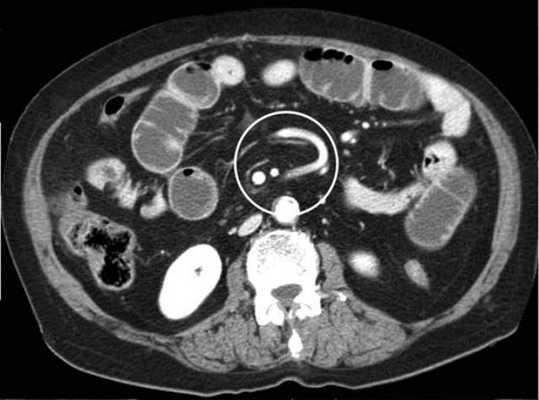

(а) При КТ с контрастированием в аксиальной проекции выявлена транспозиция верхней брыжеечной артерии (указатель) и вены (стрелка).

(б, в) На более низких уровнях при КТ в аксиальной проекции выявлен симптом «водоворота» (стрелка), представляющий собой перекручивание верхней брыжеечной вены и ее ветвей, брыжеечного жира и петель кишки вокруг верхней брыжеечной артерии по часовой стрелке.

Ультрасонография (УС) информативна при патологическом перекручивании верхних брыжеечных артерии и вены (симптом «водоворота»), выявляемом при цветном допплеровском картировании. Однако зависимость от мастерства исследователя, а также газ в тонкой кишке, мешающий исследованию верхних брыжеечных сосудов, часто ограничивают диагностическую пользу. КТ стала важным методом визуализационной диагностики, особенно при завороте тонкой кишки у взрослых. Как и при УС, характерным признаком при КТ служит симптом «водоворота», который возникает в результате перекручивания верхней брыжеечной вены и ее ветвей, брыжеечного жира, кишки и ветвей верхней брыжеечной артерии вокруг самой верхней брыжеечной артерии, чаще по часовой стрелке.

2. При завороте средней кишки определяют характерные признаки, такие как симптом «штопора» (спиральная конфигурация дистальной части двенадцатиперстной кишки и проксимальной части тощей кишки), выявляемый при рентгенографии, и симптом «водоворота» — перекручивание верхней брыжеечной вены, брыжеечного жира и кишки вокруг верхней брыжеечной артерии, выявляемый при КТ с контрастированием.